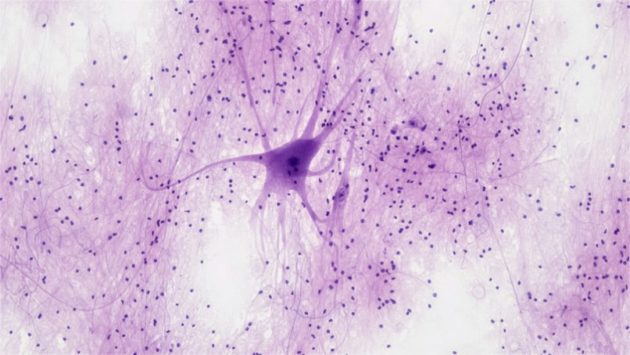

Les chercheurs proposent de modifier génétiquement des astrocytes, des cellules de soutien naturellement présentes dans le cerveau, afin qu’elles expriment des récepteurs artificiels capables de reconnaître et d’éliminer les plaques d’amyloïde-β, l’une des protéines toxiques associées à la progression de la maladie d’Alzheimer. Ces cellules modifiées agiraient comme un « médicament vivant », capable de cibler directement les dépôts pathologiques.

Contrairement aux traitements actuels basés sur des anticorps, qui circulent dans l’organisme et peuvent provoquer des effets secondaires inflammatoires, cette approche agit directement dans le cerveau. Les astrocytes possèdent en effet une capacité naturelle à engloutir et dégrader des substances étrangères, ce qui les rend particulièrement adaptés pour éliminer les plaques amyloïdes.

Les scientifiques ont utilisé un vecteur viral pour introduire dans ces cellules un gène codant pour un récepteur chimérique capable de reconnaître l’amyloïde-β. Une fois modifiées, les cellules peuvent détecter les dépôts toxiques et déclencher leur élimination tout en limitant la neuro-inflammation associée à la maladie.